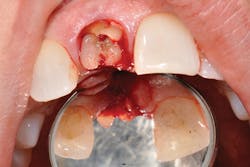

Figure 1: An X-ray revealed severe root resorption on No. 8.

A periapical of tooth No. 8 revealed my worst fears (see Figure 1). As a hygienist, as a woman, as a person who truly cares about health as well as appearance, I was devastated. Tooth No. 8 had completely failed and the root was resorbed to the point of complete instability. Everything I had been feeling and dreading the last three months was now out in the open on a giant screen in front of me. It was gaping damage and terminal.